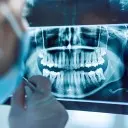

W tym wydaniu m.in: zatrzymane jedynki stałe, leczenie stomatologiczne dzieci w znieczuleniu ogólnym finansowanym przez NFZ, leczenie zapalenia przyzębia metodą niechirurgiczną, relacja drobnoustroje – przyzębie.